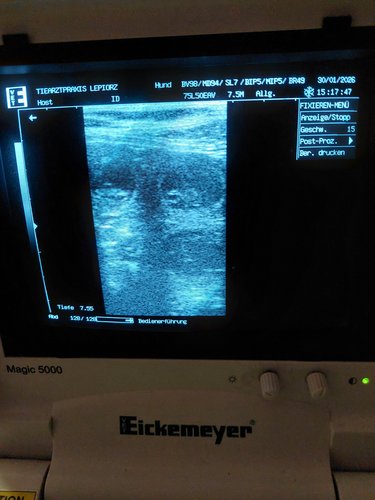

Pepper ist nun trächtig und werden euch im Aktuelles auf dem Laufenden halten.